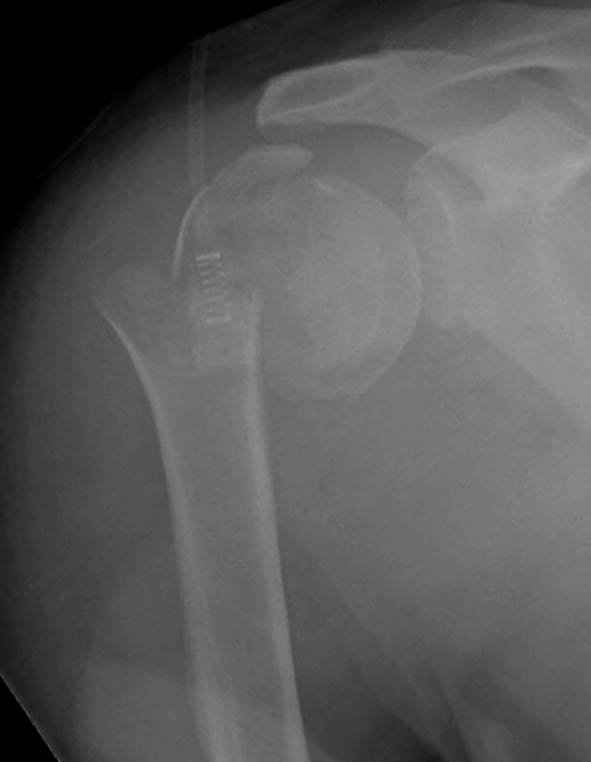

Снимки на 1-е сутки после репозиции и на 8- сутки после репозиции.

Пожалуйста

На 20-е сутки снял гипс, одел фиксирующюю

ортопедическую повязку. Вот контроль. Как видно, стояние хорошее, уже формируется костный мозоль.

Думаю еще недели 3 продолжать фиксацию.

-Головка плеча в небольшом варусе или это

проекционное?

Да, там имеем небольшой варус, надеемся, что в будущем проблемы не будет.